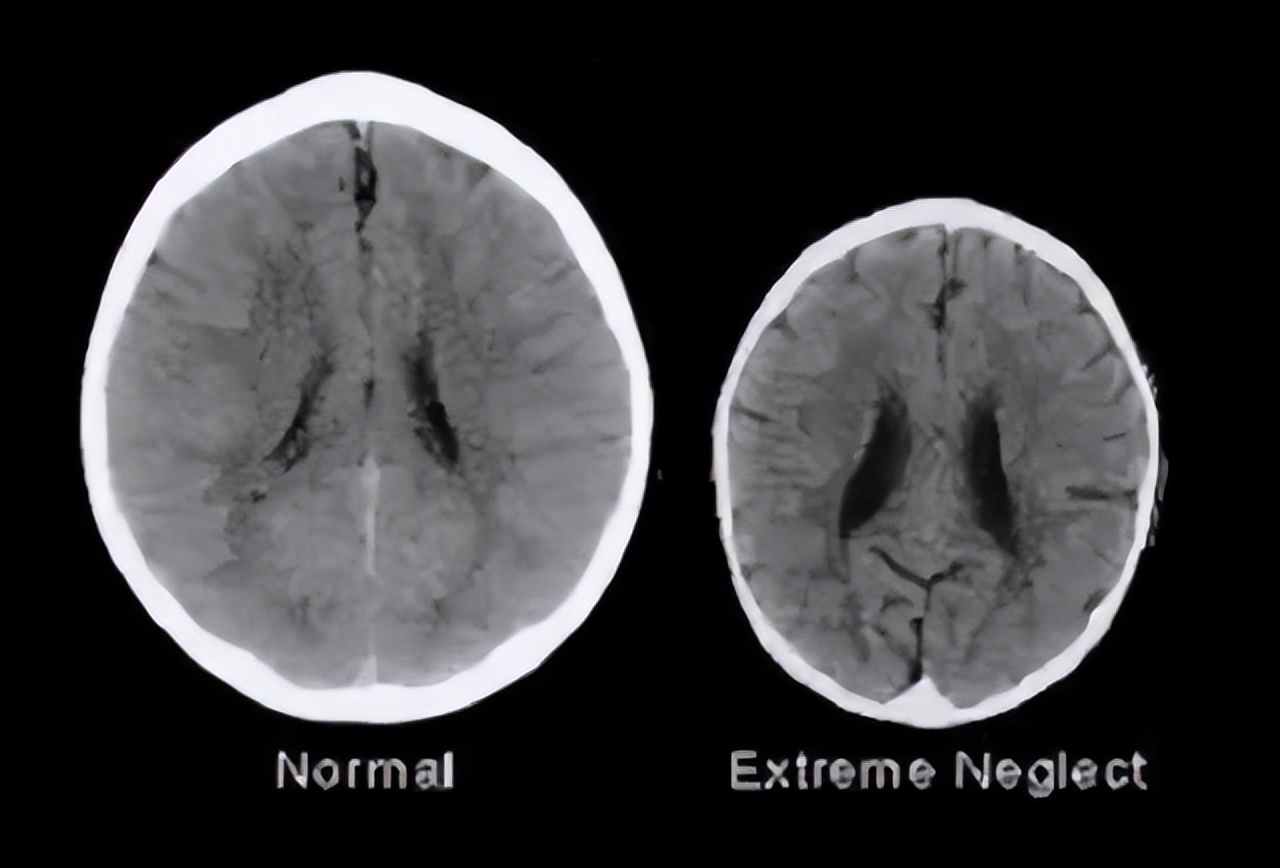

科学家曾做过一个实验。他们扫描两类年龄、性别、家境相似的孩子的大脑。结果发现,经常被吼的孩子,与少被吼骂的孩子,他们的大脑,有着巨大差异。

常被吼的孩子,他的大脑容量,明显小于没被吼的孩子大脑,并且,智力也跟着受损。